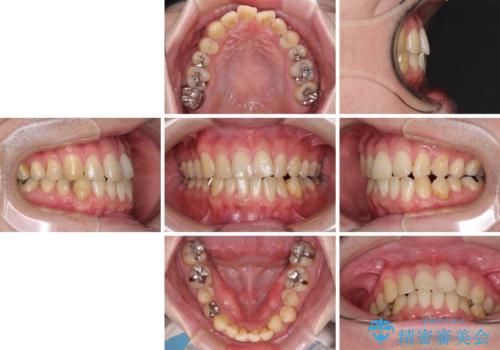

- デコボコした前歯をセラミックできれいに揃えたいとのことで来院された患者様です。

歯を削って整えることは簡単ですが、健全な歯を削って後悔してからでは遅いため、矯正治療を提案しました。

はじめは矯正治療の期間が長いことに悩んでいらっしゃいましたが、ある程度整えば満足するだろうとのことで、インビザラインにて矯正治療を行うこととしました。

左上の犬歯が欠損しているため、正中の位置や奥歯の咬み合わせが理想的にならない点を了承していただきました。

インビザライン矯正は、1日22時間を目安に装着する必要がありますが、しっかりと装着してくださったので、順調に治療を進めることができました。